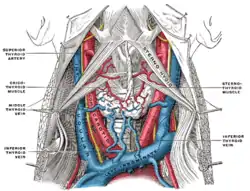

Posterior surface of sternum and costal cartilages, showing Transversus thoracis. The fascia and middle thyroid veins. The veins here designated the inferior thyroid are called by Kocher the thyroidea ima.

Sternohyoid muscle Muscles, nerves and arteries of neck.Deep dissection. Anterior view.

Muscles, nerves and arteries of neck.Deep dissection. Anterior view.